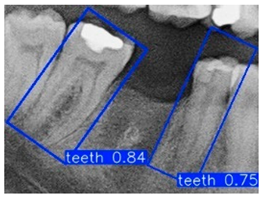

2.2.2. YOLO-OBB Architecture

3.2. YOLO-OBB Segmentation Result

| Accuracy | Precision | Recall | mAP50 | mAP50–95 | Training Time (m:s) | |

|---|---|---|---|---|---|---|

| YOLOv8n-obb | 89.80% | 89.82% | 89.98% | 89.50% | 78.75% | 21:03 |

| YOLOv10n-obb | 89.85% | 89.87% | 89.98% | 89.50% | 71.73% | 21:14 |

| YOLOv11n-obb | 89.79% | 89.98% | 89.81% | 89.50% | 77.48% | 25:12 |

| YOLOv12n-obb | 89.52% | 89.54% | 89.98% | 89.50% | 70.14% | 26:54 |